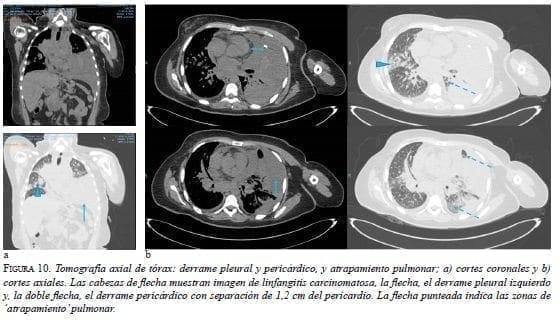

En la TC de tórax se apreciaba derrame pericárdico, con tabiques, derrame pleural izquierdo, y engrosamiento pleural y pericárdico (figura 10).